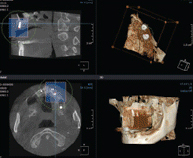

3차원 정밀진단 시스템

얼굴 골격을 빠짐없이 분석합니다

얼굴 골격의 모든 방향을 빠짐없이 촬영하고

치아와 치조골의 상태 및 잇몸뼈의 양과 길이 등의

전반적인 상태를 정확하게 측정하고 진단하여

한치의 오차 없는 시술로 진료의 안정성을 높힙니다.